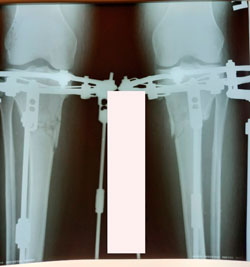

на фиксации

Вложения

image-09-12-20-01-53.jpg

image-09-12-20-01-53-1.jpg